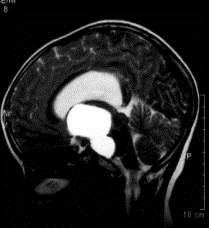

问题 病历摘要:??患者女性,6岁,半年来感觉视力模糊,近10天出现反复头痛,间有恶心呕吐,精神转差,查体:神志清楚,身高90cm,体重25Kg,血压90/55mmHg,右眼视力4.6,左眼视力4.8,双侧视乳头水肿,颈软,伸舌居中,四肢肌张力正常,肌力5级,双侧Babinski征(-)。 患者入院第三天,安排手术治疗,请选择最适用的手术入路。

选项 A.额下入路 B.翼点入路 C.终板入路 D.经胼胝体入路 E.经蝶窦入路 F.翼点-经胼胝体联合入路 G.额下-翼点联合入路 H.经脑室入路

答案 BF